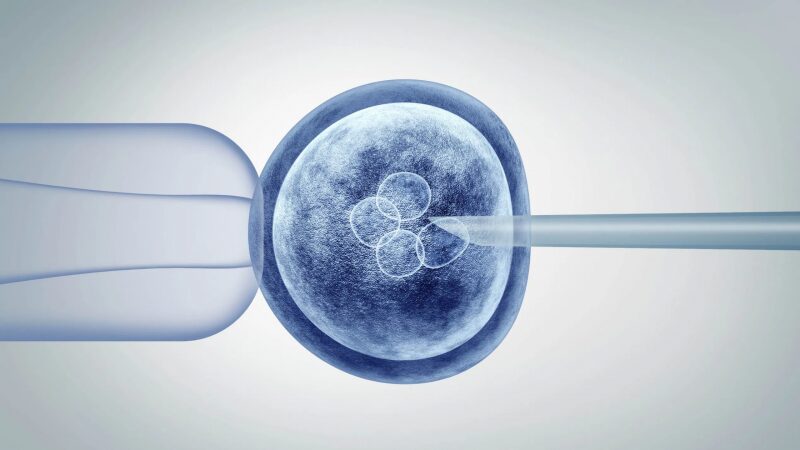

A clear guide for patients who want to understand how IVF works from ovarian stimulation to transfer.